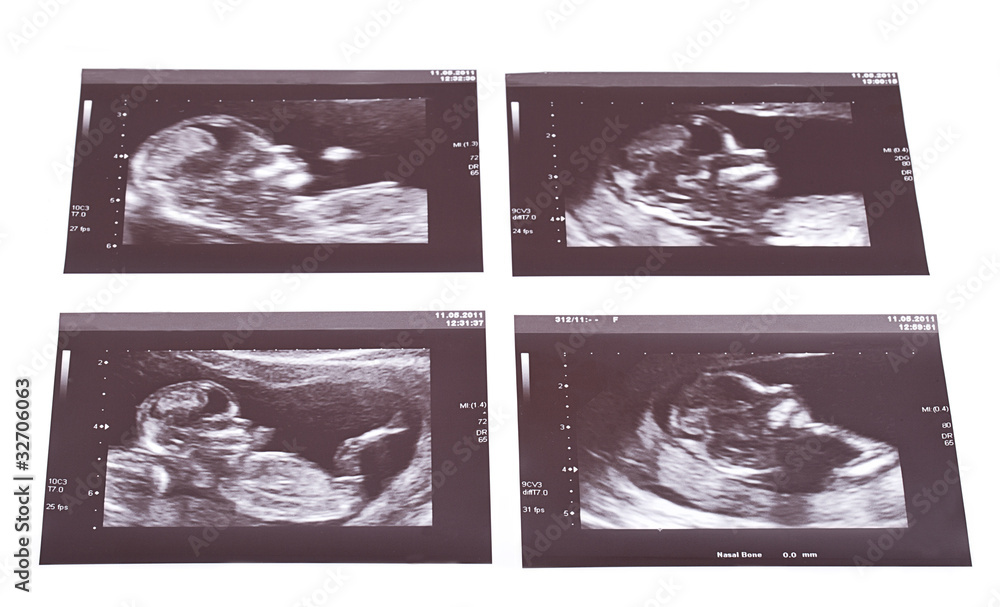

Sonogram Picture Of Identical Twins . Your ultrasound scan has shown that you are expecting twins that are monochorionic (shared placenta) or identical twins. Ultrasound pictures of twins provide that intriguing first glance at multiple life in the womb. A prenatal ultrasound is also called a sonogram and is a noninvasive diagnostic test. 10 week ultrasound of identical twins. You’ll be able to see for. All stages of twin pregnancy sonograms. There are a few variations of identical twins: Also called monoamniotic twins, these identical twins or triplets share. Check out hundreds of amazing twin ultrasound images! View the largest library of twins ultrasound images on the web. Sound waves are used to create a visual image of your babies, placenta, and uterus. A twin pregnancy can be broadly categorized into: Ultrasound assessment of fetal biometry, anatomy, doppler velocimetry and amniotic fluid volume is used to identify and monitor twin pregnancies at.

Sonogram Picture Of Identical Twins A prenatal ultrasound is also called a sonogram and is a noninvasive diagnostic test. 10 week ultrasound of identical twins. View the largest library of twins ultrasound images on the web. A twin pregnancy can be broadly categorized into: Ultrasound pictures of twins provide that intriguing first glance at multiple life in the womb. Your ultrasound scan has shown that you are expecting twins that are monochorionic (shared placenta) or identical twins. Check out hundreds of amazing twin ultrasound images! Ultrasound assessment of fetal biometry, anatomy, doppler velocimetry and amniotic fluid volume is used to identify and monitor twin pregnancies at. Sound waves are used to create a visual image of your babies, placenta, and uterus. A prenatal ultrasound is also called a sonogram and is a noninvasive diagnostic test. All stages of twin pregnancy sonograms. You’ll be able to see for. Also called monoamniotic twins, these identical twins or triplets share. There are a few variations of identical twins: